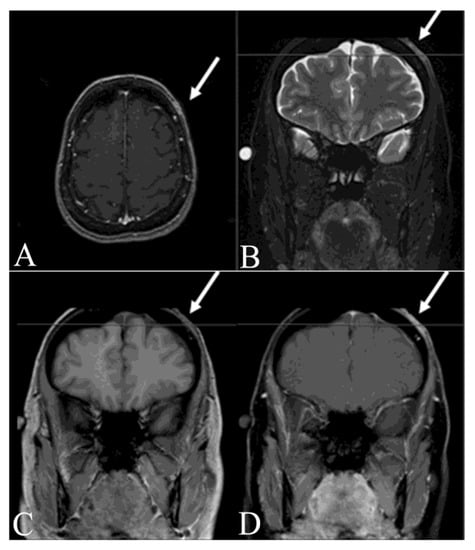

- Thornton, S.L.; Reid, J.; Papay, F.A.; Vidimos, A.T. Childhood dermatofibrosarcoma protuberans: Role of preoperative imaging. J. Am. Acad. Dermatol. 2005, 53, 76–83. [Google Scholar] [CrossRef]

- Riggs, K.; McGuigan, K.L.; Morrison, W.B.; Samie, F.H.; Humphreys, T. Role of magnetic resonance imaging in perioperative assessment of dermatofibrosarcoma protuberans. Dermatol. Surg. 2009, 35, 2036–2041. [Google Scholar] [CrossRef]

- Zhang, L.; Liu, Q.Y.; Cao, Y.; Zhong, J.S.; Zhang, W.D. Dermatofibrosarcoma Protuberans: Computed Tomography and Magnetic Resonance Imaging Findings. Medicine 2015, 94, e1001. [Google Scholar] [CrossRef]

- Torreggiani, W.C.; Al-Ismail, K.; Munk, P.L.; Nicolaou, S.; O’Connell, J.X.; Knowling, M.A. Dermatofibrosarcoma protuberans: MR imaging features. Am. J. Roentgenol. 2002, 178, 989–993. [Google Scholar] [CrossRef]